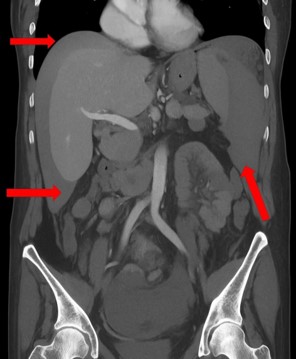

One day after the procedure, she visited the emergency department following three episodes of hematochezia and multiple episodes of near-syncope without loss of consciousness. She presented with intense abdominal discomfort, hypotension (BP=84/59 mmHg), and tachycardia (HR=110 bpm). A CT scan of the abdomen revealed a grade four splenic lesion in the middle third and free fluid in the splenic and perihepatic spaces (Figures 1 and 2).

Figure 1: Axial Computed Tomography (CT) scan showing splenic parenchymal blush with peritoneal extravasation (yellow arrows) and fluid in the perihepatic space (red arrow).